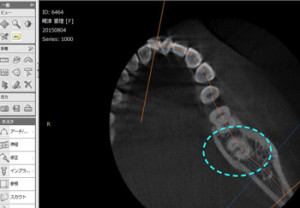

CTで親知らずを分析

コラム「CTで親知らずを分析」の画像